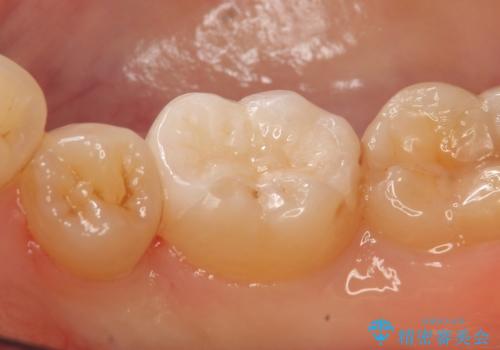

- 右下6番目の歯がしみるといらっしゃった方の症例です。

古い樹脂及び虫歯を除去後、セラミックインレーにて修復を行いました。

当院のセラミックインレーはemaxという強度と審美性に優れた材料を使用しています。

またプレス方式でインレーを製作しているため、削り出しで製作するCADCAMより優れた適合性も持ち合わせており、虫歯が再発しにくい修復物です。